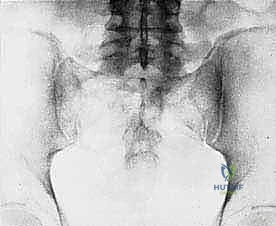

- Plain Radiography (FIG 2): While of limited value for early lesions, it provides an initial overview. As you can see in Figure 2A, we have a large lytic lesion of the right periacetabular region. Figure 2C shows a cartilage-forming lesion in the left ilium. However, plain films often underestimate the true extent of these tumors.